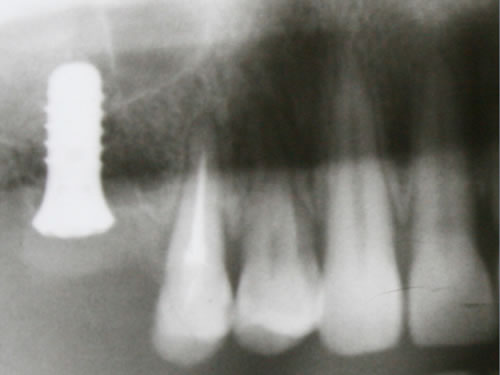

3.2 Verkürzte Zahnreihen (Freiendsituation)

Die Backenzähne sind häufig die ersten Zähne, die entfernt und ersetzt werden müssen. Wenn alle Backenzähne einer Kieferhälfte fehlen, spricht man von einer verkürzten Zahnreihe oder einer Freiendsituation. Hier fehlt der für eine Brücke notwendige hintere Pfeiler (Abb. 3.19 bis 3.21).

Mit Hilfe künstlicher Zahnwurzeln kann bei derartig verkürzten Zahnreihen im Unterkiefer eine Brücke ­angefertigt werden. Damit lassen sich das "Herunterwachsen" oder "Heraufwachsen" (Elongation) der Gegenzähne so wie das Kippen verhindern und die Kaufunktion mit einem festsitzenden Zahnersatz wiederherstellen.